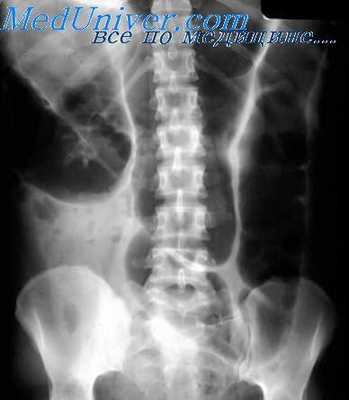

Скопление газа и жидкости. Одновременное скопление в кишечнике жидкости и газа сопровождается образованием одиночных или множественных горизонтальных уровней с газовыми пузырями над ними — чаш Клойбера. Количество, величина и форма этих чаш колеблются в широких пределах и зависят от многих причин, в частности от их местоположения и характера патологического процесса. Так, тонкокишечные чаши Клойбера имеют небольшие размеры, чаще множественны, располагаются в центральных отделах брюшной полости. Длина каждого уровня обычно больше высоты расположенного над ним газового пузыря. В толстой же кишке, наоборот, небольшие горизонтальные уровни жидкости сочетаются с высокими газовыми пузырями и располагаются в периферических отделах брюшной полости. При этом преобладает вздутие петель газом, на фоне которого обычно хорошо видны гаустральные перетяжки. Число же горизонтальных уровней жидкости остается небольшим. Если же большое количество газа скапливается в тонкой кишке, то раздутые им петли образуют своеобразные арки с поперечной симметричной исчерченностью, обусловленной циркулярными (керкринговыми) складками.

Выявляется этот синдром главным образом при непроходимости кишечника как механической, развивающейся вследствие сужения просвета кишки на почве опухолей, Рубцовых изменений кишечной стенки, заворота, инвагинации и других причин, так и динамической, возникающей рефлекторно при различных патологических процессах в брюшной полости и забрюшинном пространстве (аппендицит, панкреатит, перитонит и др.). Может наблюдаться при остром холецистите, энтерите, энтероколите и язвенном колите, а также в послеоперационном периоде. Распознается при бесконтрастном полипозиционном рентгенологическом исследовании, а также при введении в кишку контрастных веществ с помощью дуоденального зонда (энтерография) или клизмы (ирригоскопия).